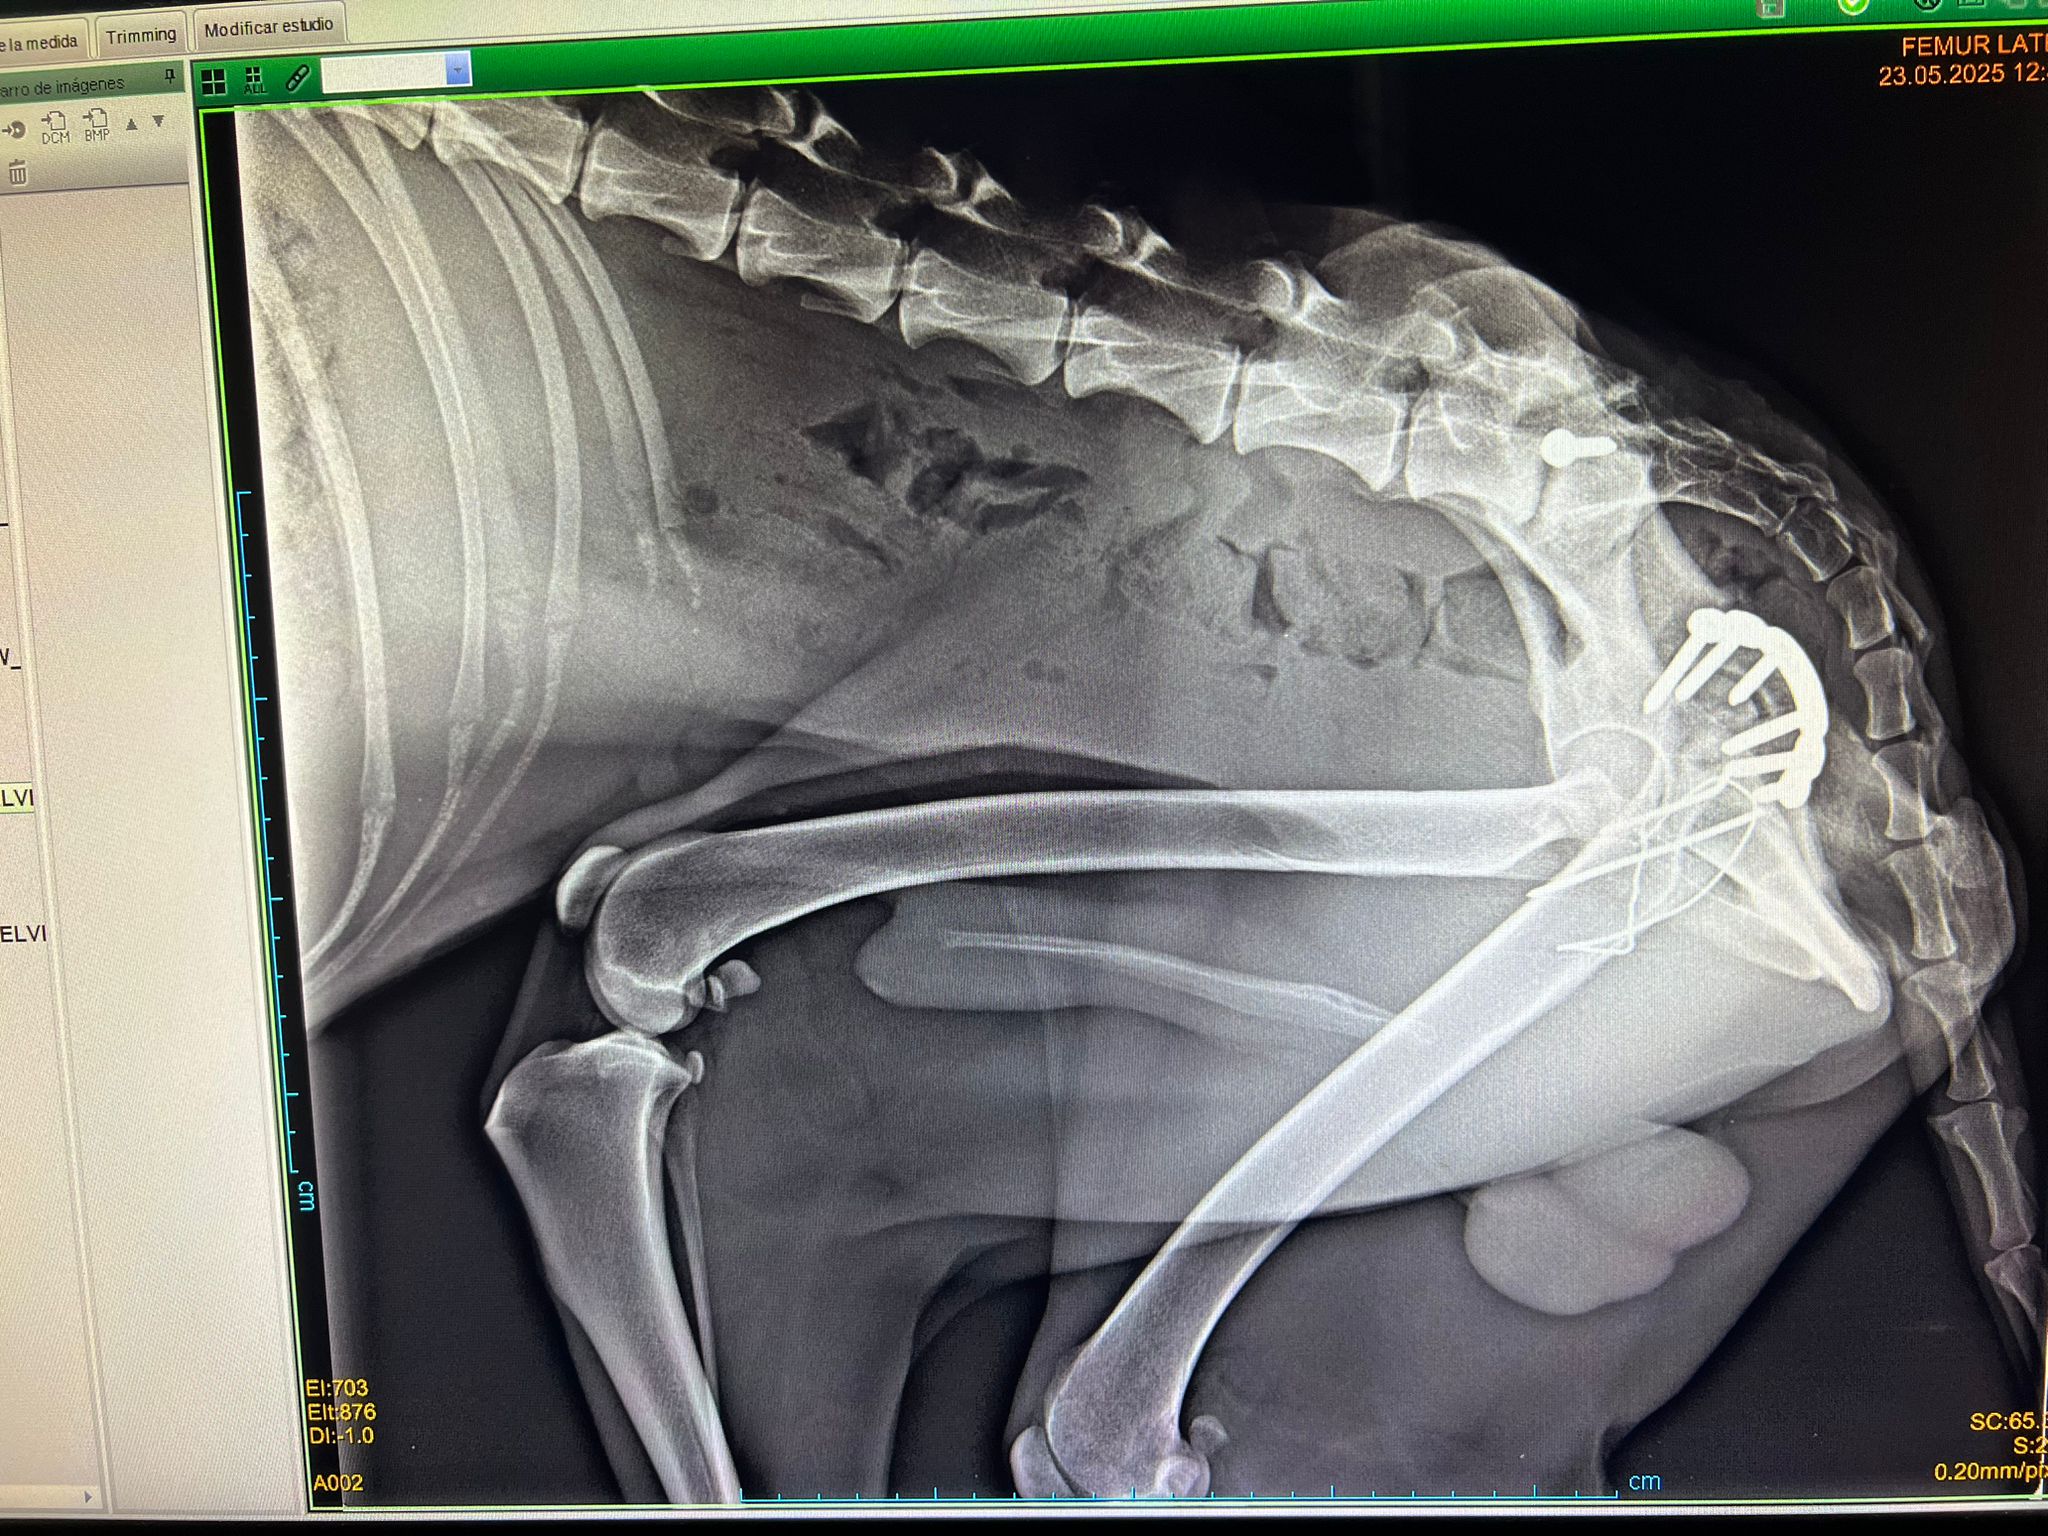

Lucio fue adoptado de un centro de recogida de Toledo. Cuando llegó, estaba muy delgado y tenía dos fracturas por un recogieron atropellado. Ya lo operaron de estas fracturas y se encuentra muy bien.

Lucio was taken over from another rescue in Toleda. When Lucio arrived, he was very skinny and had two fractures because he was hit by a car. He’s been operated on these fractures and is doing very well.